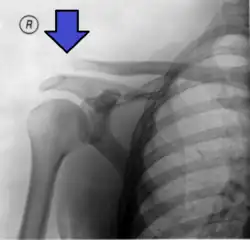

![]() | |

| An Xray showing a separated shoulder. Notice the separation between the end of the collarbone and the scapula. | |

X-ray indicates a separated shoulder when the acromioclavicular joint space is widened (it is normally 5 to 8 mm).[9]